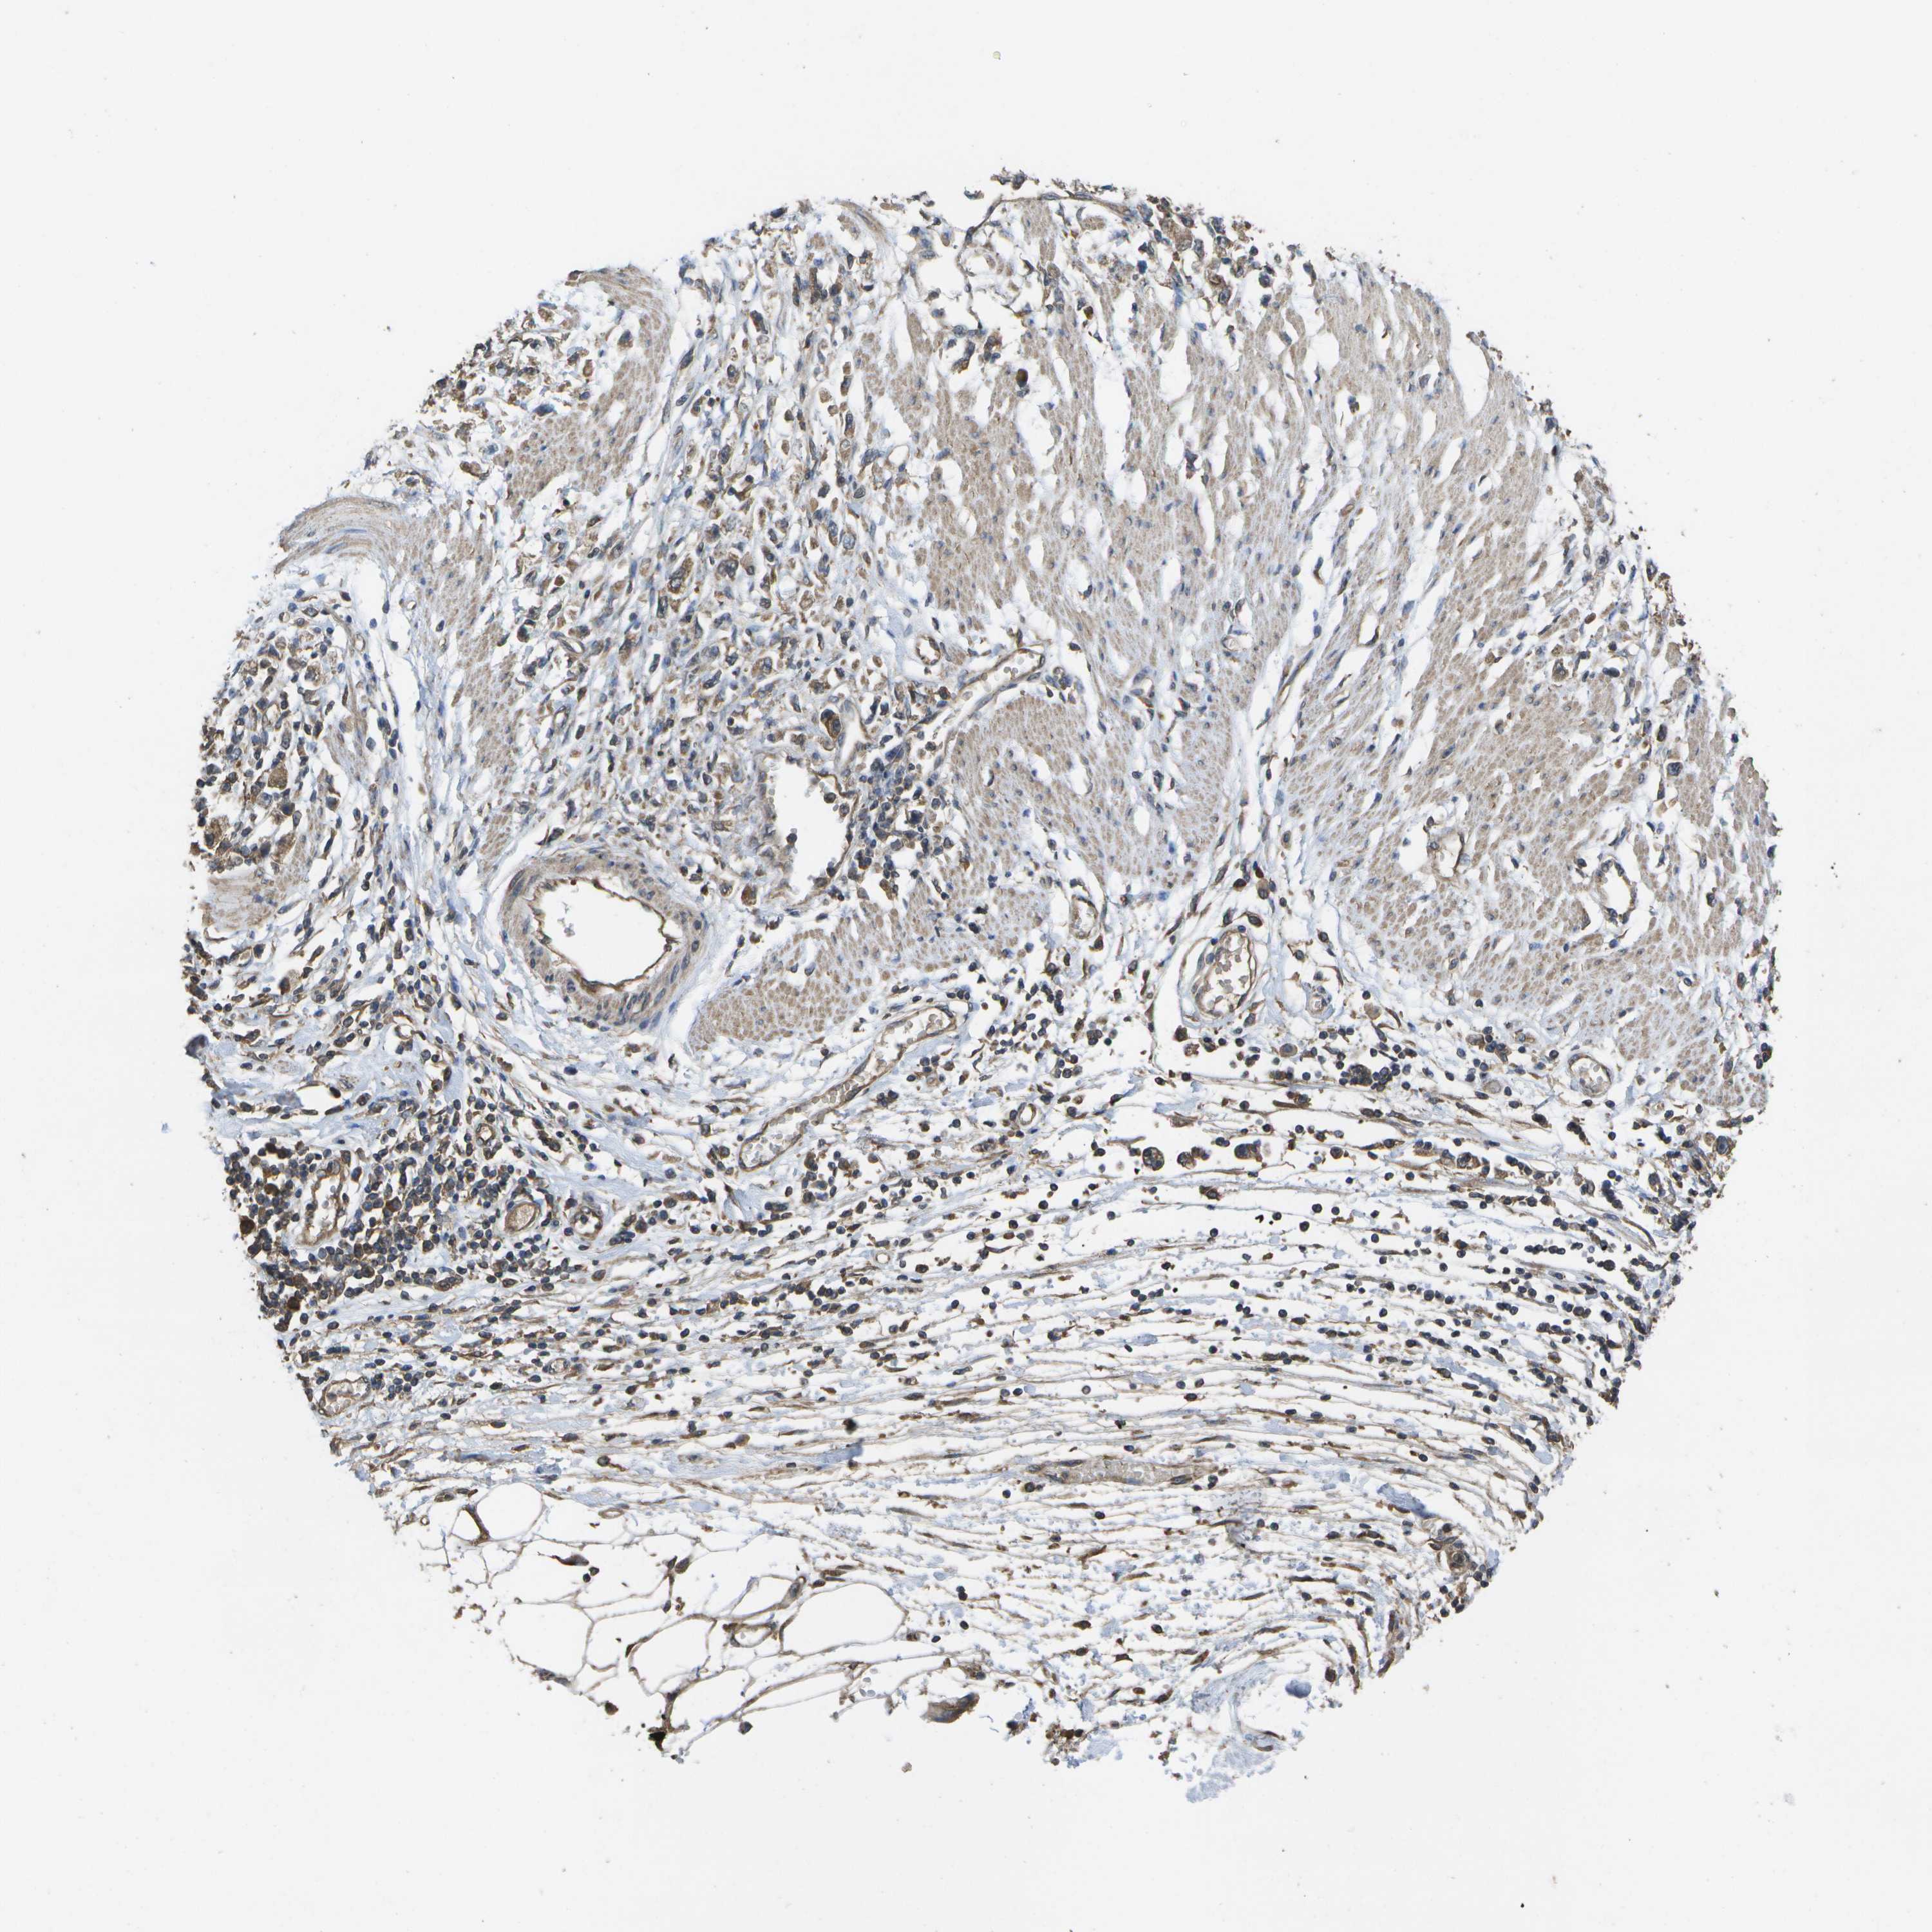

STOMACH CANCER - Protein expressioni

A mouse-over function shows sample information and annotation data. Click on an image to view it in a full screen mode. Samples can be filtered based on level of antibody staining by selecting one or several of the following categories: high, medium, low and not detected. The assay and annotation is described here.

Note that samples used for immunohistochemistry by the Human Protein Atlas do not correspond to samples in the TCGA dataset.

Antibody stainingi

Antibody staining in the annotated cell types in the current human tissue is reported as not detected, low, medium, or high, based on conventional immunohistochemistry profiling in selected tissues. This score is based on the combination of the staining intensity and fraction of stained cells.

Each image is clickable and will lead to virtual microscopy that enables deeper exploration of all samples and also displays staining intensity scores, fraction scores and subcellular localization as well as patient and tissue information for each sample.

Antibody CAB017714

Staining

High

Medium

Low

Not detected

Intensity

Strong

Moderate

Weak

Negative

Quantity

>75%

75%-25%

<25%

None

Location

Nuclear

Cytoplasmic/membranous

Cytoplasmic/membranous,nuclear

Adenocarcinoma, NOS

Adenocarcinoma, High grade